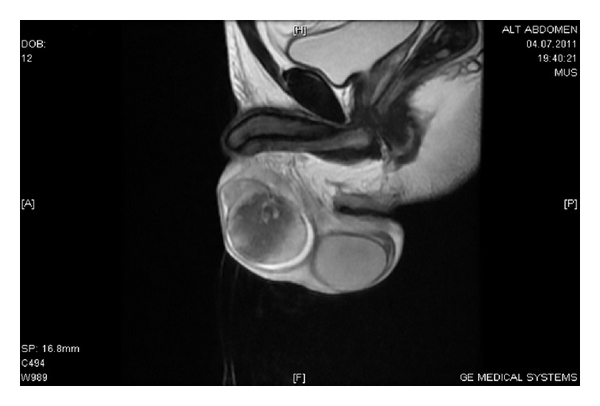

The scrotal color Doppler US and scrotal MRI scan were performed for the differential diagnosis of possible testicular abscess and masses (Figures 1 and 2). While two patients were treated with doxycycline mg PO and rifampicin mg IV, 5 patients underwent streptomycin gr IM and doxycycline mg PO treatment over 6 weeks. 3 BEO patients with coexisting spondylitis had also sacroiliitis at the same time. These patients were treated with streptomycin gr IM and doxycycline mg PO combination during 2 weeks and subsequently doxycycline mg and rifampicin mg treatment regime was used in the following 3 months. Three patients with no skeletal involvement were treated with streptomycin gr IM during 2 weeks and doxycycline mg PO during 6 weeks.